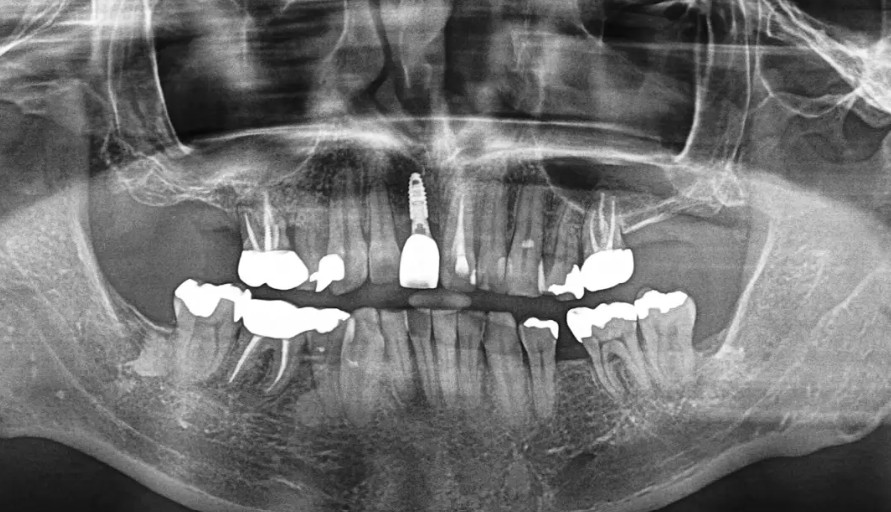

歯科医院4件断られた全顎的な治療(インプラント・セラミック)

主訴 歯並びが悪くなって食事がしずらい。 食事を美味しく食べられるようになりたいし時間をかけずに専門の先生でしっかり治したい。 通院期間・回数 回数10回 治療内容 サイナスリフト:330,000円 インプラント:495 […]